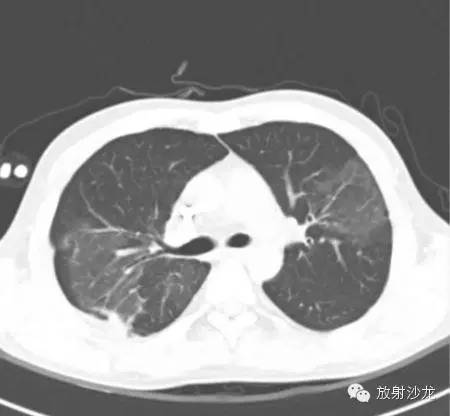

(第一次胸片示两肺中野及右肺下野多发斑片状高密度影。胸部CT示多发斑片状磨玻璃样密度增高影以及实变影,同时伴有小叶间隔的增厚。其中有些病灶部分表现为“铺路石征”。两周后CT随访显示这些病灶的密度和范围都增大。电视辅助胸腔镜肺活检下,活检标本病理诊断结果为急性纤维素性机化性肺炎。上述病变经高剂量糖皮质激素治疗三周后明显改善。)

大量急性纤维素性机化性肺炎的影像学显示已经累及双肺,并存在弥漫浸润性病变,双肺还表现出弥漫斑片状实变阴影改变,一般双侧肺底比较多见,部分患者出现单侧结节状实变阴影, 很容易将其与结核、肿瘤等混淆。急性纤维素性机化性肺炎组织学特征主要是肺泡腔内沉积大量纤维素,同时形成均质嗜酸性的纤维素球,少数患者的纤维球周边出现新的纤维组织。